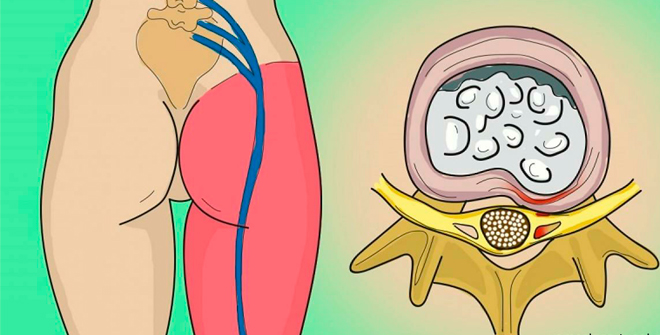

→ Экстрагенные вещества цветочной пыльцы обладают выраженным противовоспалительным действием при патологических изменениях предстательной железы.